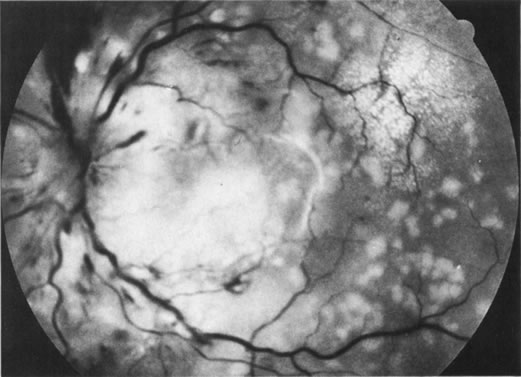

Necrotic melanomas account for approximately 5% of uveal melanomas; in the majority of cases, there is intraocular inflammation accompanying the cataract.7–9Figures 1 and 2 demonstrate a typical case. The patient had a long history of unilateral decreased vision. The eye had become painful 1 month before admission, and he was referred for evaluation of uveitis. Clinically, there was a dense, unilateral cataract with significant intraocular inflammation, which was manifested as a ciliary flush with 2+ cells and flare. Media opacity obscured all fundus detail. An immersion B-scan demonstrated a large intraocular tumor that was most consistent with a uveal melanoma. The eye was removed, and the diagnosis was confirmed histologically.10

Unfortunately, imaging studies are not always diagnostic. The A- and B-scans shown in Figures 3 and 4 were from a patient with unilateral media opacity referred for evaluation and treatment of a presumed uveal melanoma. Occasionally, if the cataractous lens is scanned tangentially, artifact can occur. A repeat ultrasound at our institution was negative for tumor, and the referral ophthalmologist who performed a cataract extraction noted that no tumor was present and that the patient has an excellent visual outcome. In contrast, the patient shown in Figure 5 was referred with a presumed uveal melanoma with secondary inflammation and a history similar to that described for the patient shown in Figure 111 Ultrasound and CT examinations were not diagnostic. Because the eye was blind and painful, it was enucleated, and an extremely necrotic uveal melanoma was noted histologically. In some necrotic melanomas, the fundus cannot be visualized and the diagnosis cannot be established with imaging studies. Very rarely, a necrotic uveal melanoma can produce sufficient pigment dispersion into the vitreous to obscure the correct diagnosis.12